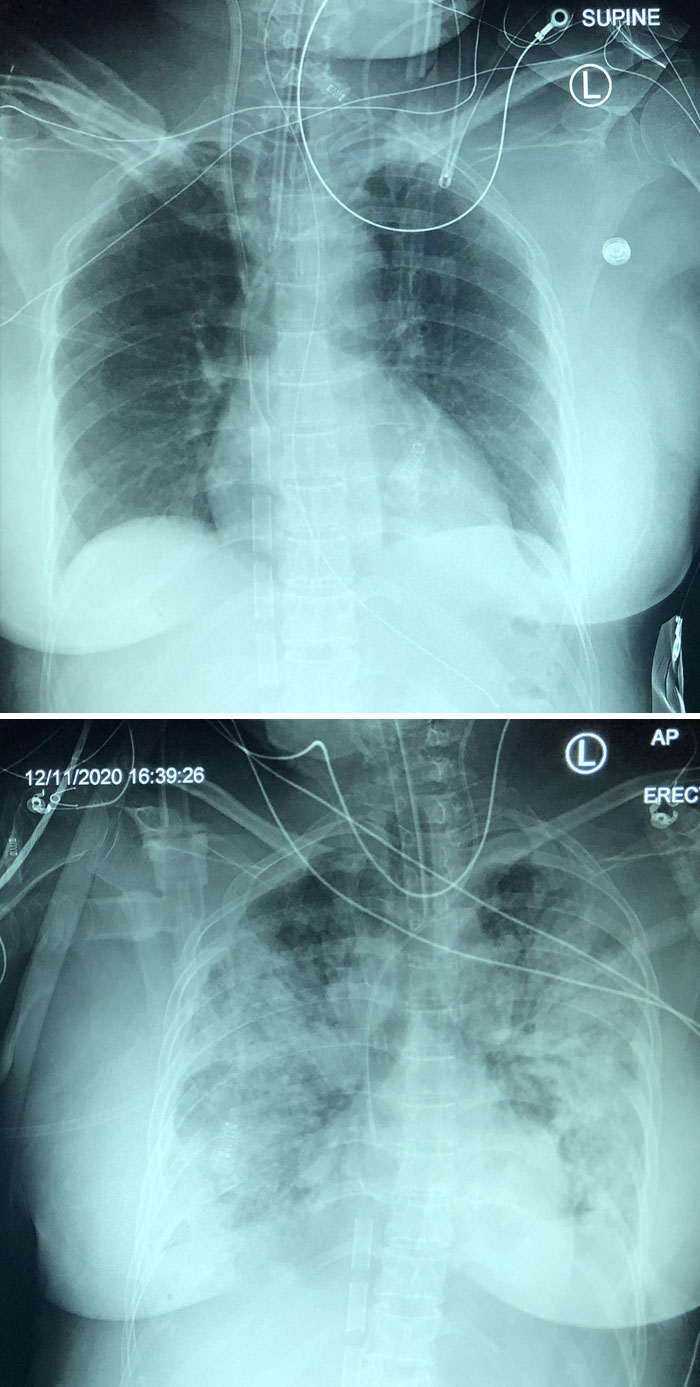

5-Day Progression Of Covid Pneumonia

I Took This X-Ray On A Covid+ Patient Hours After My Friend Tried To Tell Me Covid Isn't That Bad